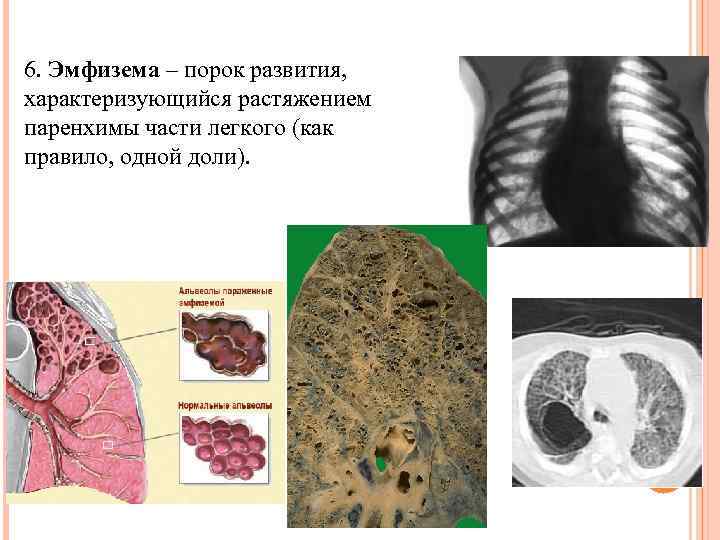

6. Эмфизема – порок развития, характеризующийся растяжением паренхимы части легкого (как правило, одной доли).

6. Эмфизема – порок развития, характеризующийся растяжением паренхимы части легкого (как правило, одной доли).